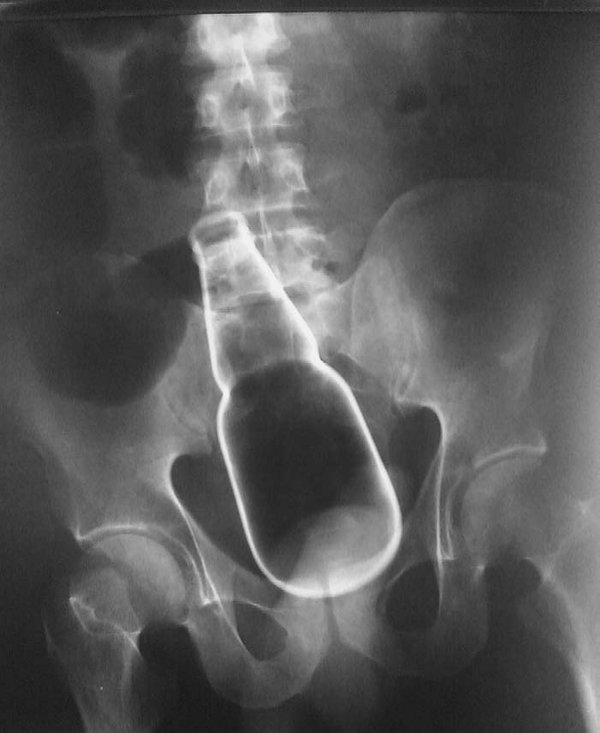

Re: Un chien filmé en fluoroscopie pendant qu'il mange

Un peu dérangeant à voir mais intéressant ! Ca va plus vite que je n'imaginais et au final tant mieux...

Bref ils l'ont bien irradié, ce n'est pas pour rien que l'on ne s'amuse pas à faire cela

On dirait un bulldog francais tiens .

maintenat tout le monde comprend la forme des crottes de chien. c'est des le depart que cela se forme